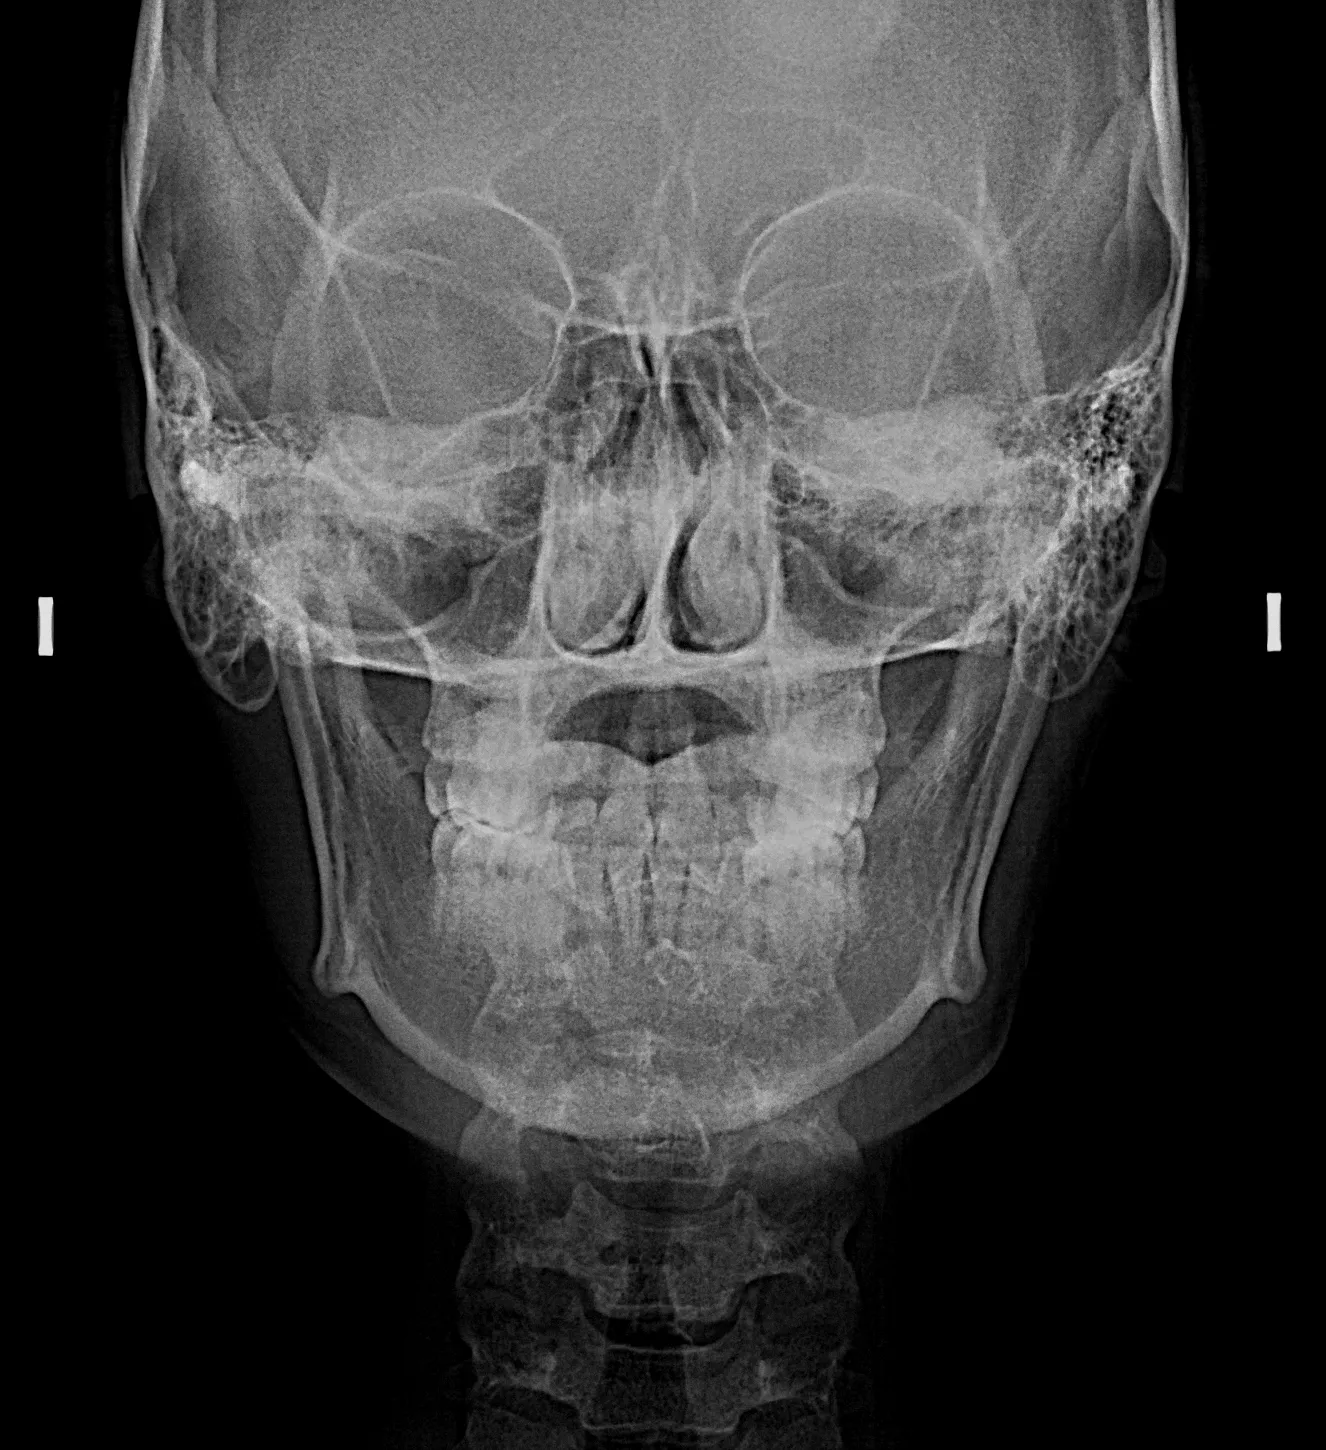

Las radiografías extraorales permiten obtener imágenes completas de los maxilares, la articulación temporomandibular (ATM) y las estructuras faciales sin colocar el sensor dentro de la boca.

Realizamos estudios como radiografía panorámica, cefalométrica, de senos paranasales y de ATM, esenciales para tratamientos de ortodoncia, cirugía y diagnóstico integral.